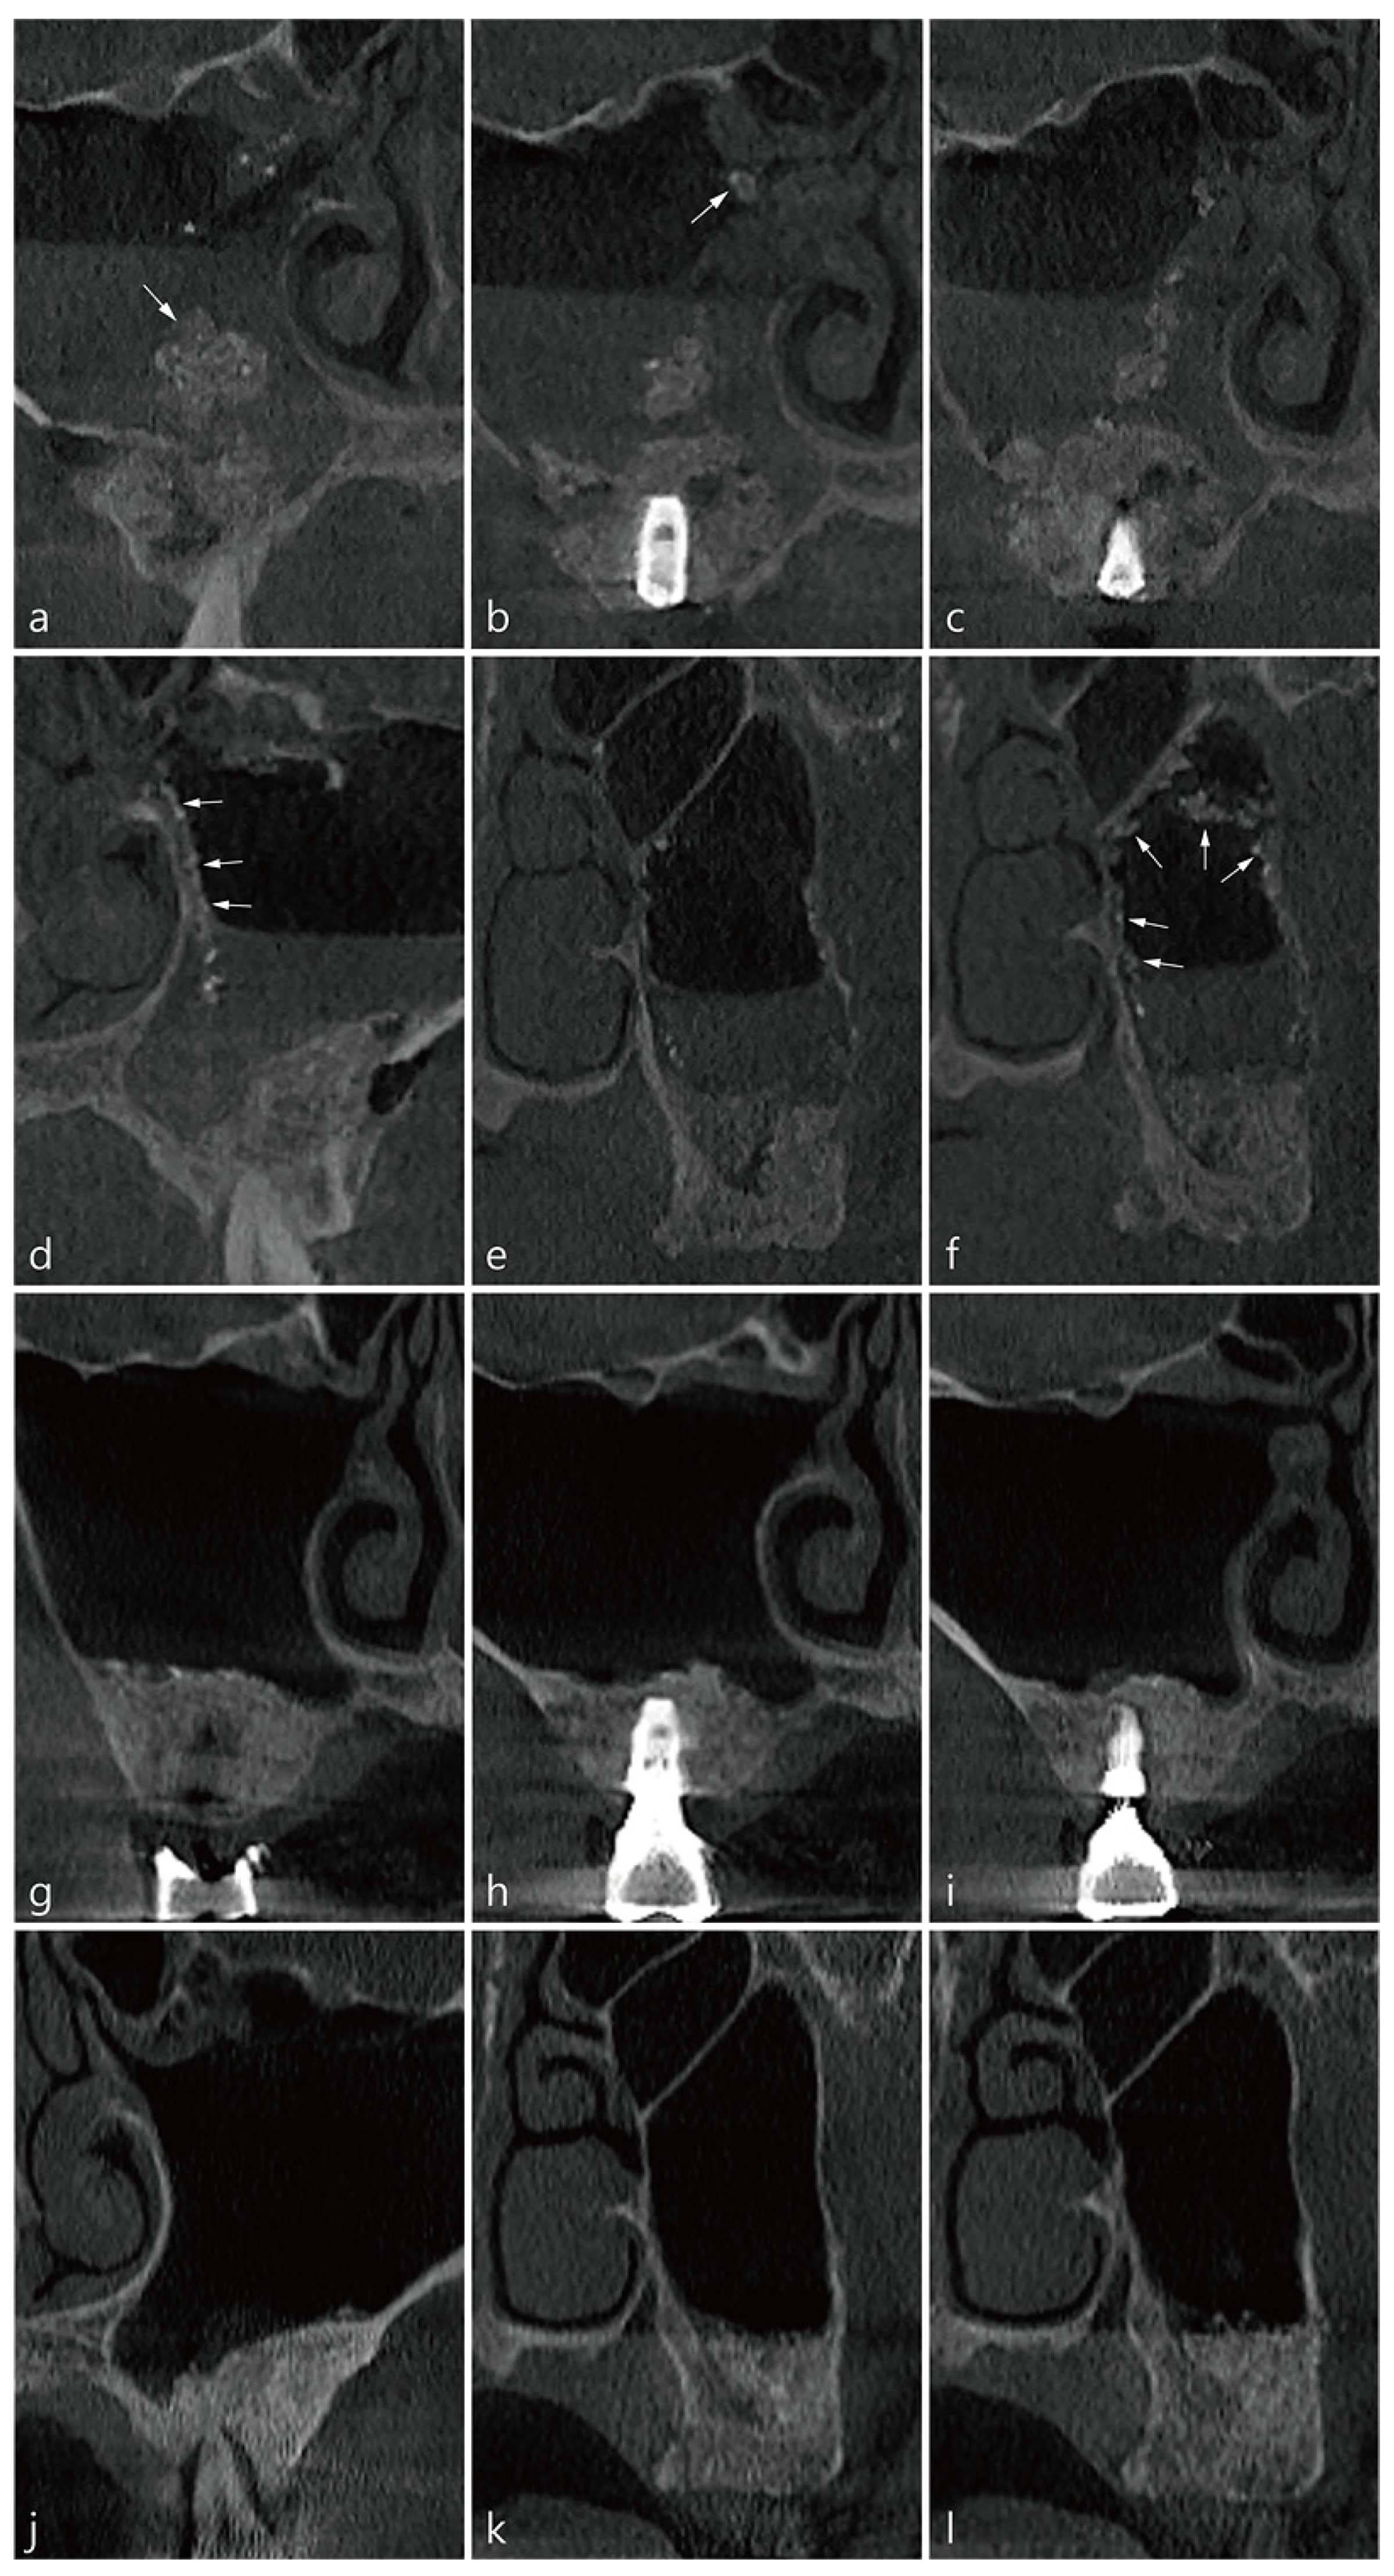

2. Presentation of Cases

3. Case 1

4. Case 2

5. Case 3

6. Case 4